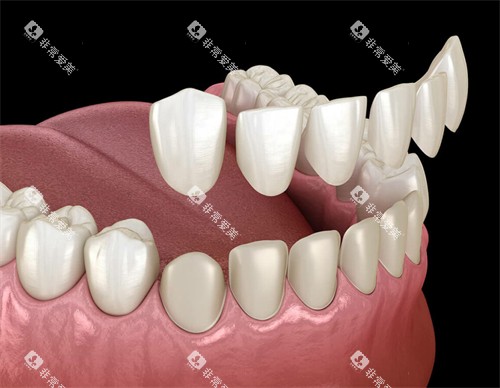

易美口腔一进门就像穿越到科幻片现场——全智能化设备、3D口腔扫描仪、隐形矫正模拟系统……妥妥的“黑科技代言人”。这里主打准矫正,尤其是隐形牙套(隐适美、时代天使)患者,医生会通过AI模拟提前预览矫正改善,连笑线弧度都能调整到“较好角度”。

智能化诊断全:拍片、方案设计不花钱,先看改善再决定,社恐人士也不用担心被“强行推销”。

矫正周期缩短30%左右:科技加持下,传统矫正2年的疗程可能压缩到1年半,省时=省钱!